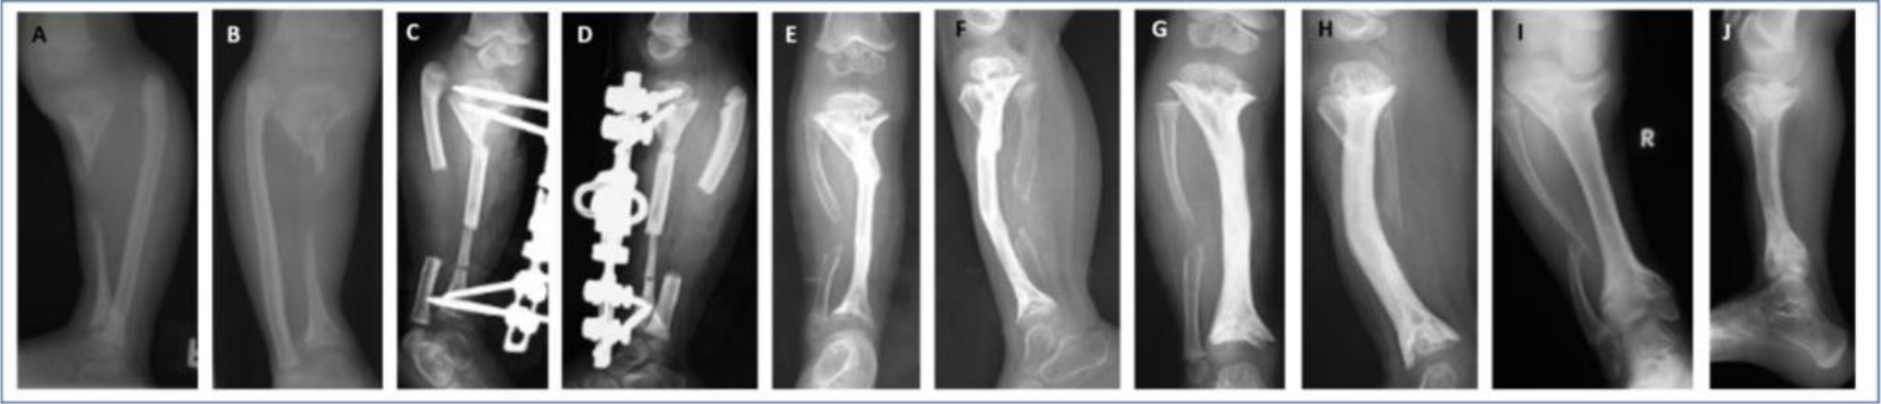

https://jbji.copernicus.org/articles/10/155/2025/jbji-10-155-2025-f01

Figure 1An 8-year-old boy with a 5-month history of untreated, spontaneous infection of the left radius. At presentation, the sequestrated radius was partly extruded (a). Radiographs showed the sequestration of the entire diaphysis, with a large bone defect (b, c). Reconstruction stage 1 required sequestrectomy (debridement) and positioning of a paediatric Orthofix rail (d). After surgery, the bone ends were gradually distracted to restore the radial length and the distal radius–ulna joint relationship (e). One month later, a long tibial strut was employed, tightly inserted between the bone ends and stabilized by a new external fixator (f, g). Post-operative radiographs were taken 70 (h), 120 (i) and 210 (j, k) days after stage 2. It took 7 months to achieve the cylindrical transformation of the strut, with excellent integration at both ends. Radiographs at 11 years after surgery showed full radial integration and remodelling (l, m). Excellent bone and functional results were obtained.

https://jbji.copernicus.org/articles/10/155/2025/jbji-10-155-2025-f02

Figure 2A 2-year-old child with a severe case of haematogenous femoral osteomyelitis presenting 2 months after the onset of symptoms. Radiographs showed sequestration of the entire diaphysis, pathological fracture and physeal involvement (a, b). Debridement and stabilization with an external fixator were performed, leaving the sequestrum in situ (c). This allowed better demarcation of the sequestrated segment and time for development of periosteal involucrum. This is common in small children. Sequestrectomy was performed 3 months later. Ten months later, the child presented with a bone defect in the mid-femur without any sign of infection (d). A tibial cortical strut graft was placed and secured by trans-osseous stitches. An external fixator was reapplied (e). Sound integration of the graft was observed at 16 weeks (f) and the fixator was removed. Radiographs are shown 1 year after the graft procedure (g, h). Graft hypertrophy and cylindrical transformation of the graft were noted, together with early closure of both physes, deformity of the femoral condyles and patella baja. An orthoprosthesis for the leg length discrepancy (LLD) was fabricated. At 8 years, he was walking without aids or a shoe raise. He had a 17 cm LLD and no infection relapse. The radiographs showed a short femur, knee deformity and patella baja (i, j, k).

https://jbji.copernicus.org/articles/10/155/2025/jbji-10-155-2025-f03

Figure 3A 2-year-old girl presented with severe osteomyelitis and an exposed sequestrum. The infection was quiescent at presentation. Radiographs showed a short deformed leg, a large bone defect of the tibia and early physeal closure (a, b). Amputation was advised but was refused. A segment of the ipsilateral fibula was inserted between the trimmed bone ends, with concurrent axis correction and external fixation (c, d). At 13 weeks, the graft is integrating and remodelling (e, f). Radiographs at 14 months showed a short, sclerotic tibia with moderate procurvatum (g, h). An orthoprosthesis was prescribed. Ten years later, she had no infection relapse, just moderate knee and ankle pain with a severe LLD (15 cm). She walked normally without aids or a brace. The radiographs showed a short tibia with varus deformity due to medial tibial plateau depression (i, j).

https://jbji.copernicus.org/articles/10/155/2025/jbji-10-155-2025-f04

Figure 4A 12-year-old boy presented with complicated tibial osteomyelitis with an exposed sequestrum, pathological fracture as well as bone and soft tissue loss. Radiographs showed sequestration of the central shaft of the tibia (a, b). Sequestrectomy was performed, and the tibia was stabilized with an external fixator. A proximally based hemisoleus flap was transferred 2 weeks after the debridement (c, d, e). Three months later, a tibial cortex strut was inserted (f, g). The fixator was removed 6 weeks later and replaced with a long-leg cast. Radiographs are shown at 4 months after grafting (h, i). Seven years later, they showed full graft integration, no infection recurrence and moderate varus of the ankle. (j, k, l) The patient reported moderate pain in the knee and ankle joints after long walks. The LLD was 7 cm, but the patient refused any shoe raise. Proposal for further surgery for lengthening was put on hold by the family.

https://jbji.copernicus.org/articles/10/155/2025/jbji-10-155-2025-f05

Figure 5A 2-year-old girl presented 2 months after spontaneous onset of infection, with an exposed sequestrum, pathological fracture and loss of soft tissues (a, b). Sequestrectomy and external fixation were carried out (c, d), leaving the skin to heal by secondary intention. Pin loosening required a change in the frame, but two proximal screws were erroneously inserted into the upper physis (e, f). Six months after the initial debridement, a tibial cortex strut was inserted and the fixator was replaced (g, h). Radiographs are shown at 5 (i, j) and 7 (k, l) months of grafting. Sound graft incorporation and bone modelling may be observed. Seven years later, at the age of 12 years (m, n, o). Closure of the upper tibial physis led to a LLD of 2 cm and deformity of the tibial plateau. However, good bone and functional results were achieved in the long term.